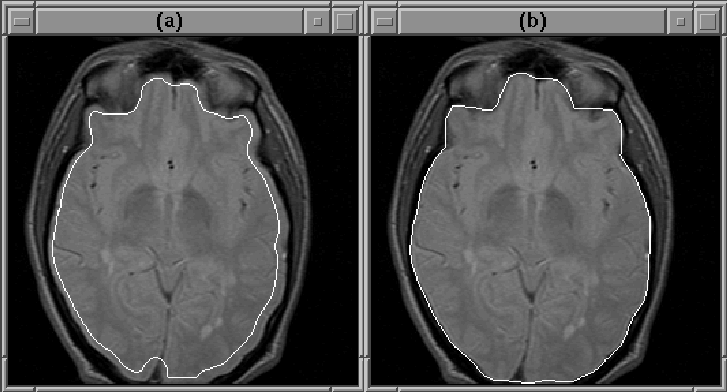

Figure 8.18: A closeup of slice 13 of MRI Data Set 1. The Generate Final Brain Mask process enlarges the initial brain mask, (a), to cover the entire brain, (b).

The intracranial boundary defined by the final brain mask of Data Set 1 is overlaid on the PD-weighted MR volume in Figure 8.17. The mask outlines the brain remarkably well in all slices. Figure 8.18 shows slice 13 at a higher resolution. Notice that the final mask covers the entire brain, whereas the initial mask lies inside the brain.